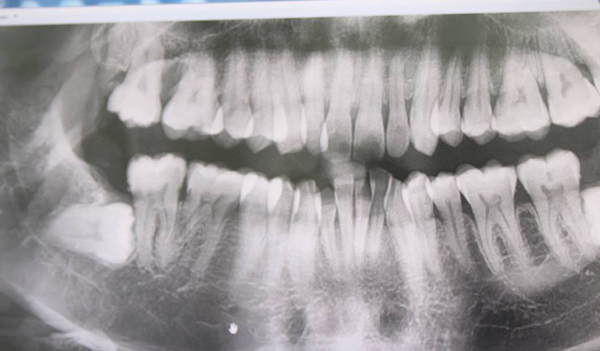

Ngày 19/7 vừa rồi, một fanpage tại Thái Lan đã chia sẻ hình ảnh một hàm răng đang được đeo niềng. Nhưng không giống như bình thường, hàm trên của người niềng chĩa thẳng ra khỏi miệng, thậm chí lộ hết chân răng bên trong. Hình ảnh này lập tức nhận được sự quan tâm lớn của cộng đồng mạng châu Á.

Được biết, hàm răng "lỗi" bên trên là tác phẩm của một bác sĩ nha khoa không được cấp phép tại Philippines. Khi khách hàng đến làm răng, đã được bác sĩ lắp móc cài và dây thép như bình thường nhưng không may lực tác dụng của dây thép này quá lớn, đã khiến hàm răng của cô gái bị kéo ngửa ra ngoài. Điều đáng buồn là hàm răng này không có cách nào quay trở lại như trước được nữa.

Nghe có vẻ đơn giản nhưng thực tế cho thấy phương pháp điều trị này rất phức tạp và khó khăn cần đến những bệnh viện, bác sĩ uy tín, nhiều kinh nghiệm. Người bị điều chỉnh nha không đúng có thể khiến răng bị nghiêng, các răng không khít nhau, làm mất thẩm mỹ và dễ tái phát, ăn uống khó khăn, hay bị mỏi, đau khớp hàm… Nếu người làm không có kinh nghiệm còn có thể khiến bệnh nhân bị lòi chân răng, viêm tuỷ răng, răng lung lay, thời gian điều trị kéo dài.